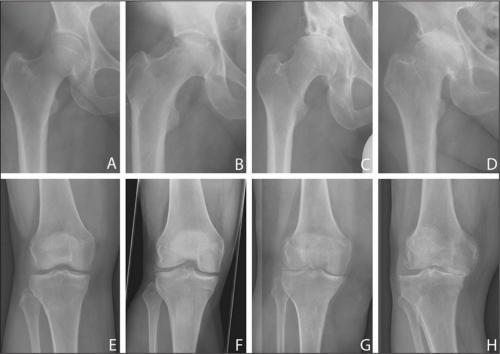

Суставная жидкость при коксартрозе густая, вязкая. Изменение консистенцииприводит к высыханию поверхности гиалинового хряща, потери им гладкости и прочности. Появление на ней трещин становится причиной постоянного травмирования хрящей при движении, их истончения, усугубления патологических изменений в тазобедренном суставе. Затем начинают деформироваться кости, пытаясь «приспособиться» к увеличению на них давления. В результате ухудшается обмен веществ, провоцируя прогрессирование деструкции, а впоследствии — и атрофию мышц ноги.

Стадии развития коксартроза ТБС.

Факторами, способствующими суставному разрушению, являются высокие физические нагрузки, малоподвижный образ жизни, патологии позвоночника (кифоз, сколиоз), гормональные расстройства, нарушения кровообращения.

Клиническая картина

Основные симптомы разрушения тазобедренного сустава — сначала редкие, а по мере прогрессирования патологии — сильные, постоянные. Они могут иррадиировать, лодыжку,,позвоночника. На приеме у ортопеда пациенты жалуются на скованность движений. Причем на начальной стадии коксартроза ограничение подвижности кратковременное, исчезающее через 1-2 часа. Человек «расхаживается», и в течение дня скованность при движении его не беспокоит. А вот на третьей стадии дегенеративно-дистрофической патологии для ходьбы больной использует трость или костыли. Нередко он не способен передвигаться по комнате без посторонней помощи. Полная или частичная утрата подвижности сопровождается укорочением ноги и атрофией бедренных мышц.

Динамика разрушения.